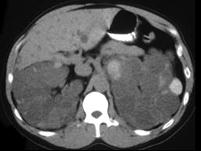

女,52岁,腰部酸胀,根据影像图像,判断其最可能的诊断 ( )A、肾脓肿B、肾盂癌伴出血C、肾细胞癌D、多囊肾E、多房性肾囊肿

问题 女,52岁,腰部酸胀,根据影像图像,判断其最可能的诊断 ( )

选项 A、肾脓肿 B、肾盂癌伴出血 C、肾细胞癌 D、多囊肾 E、多房性肾囊肿

答案 D